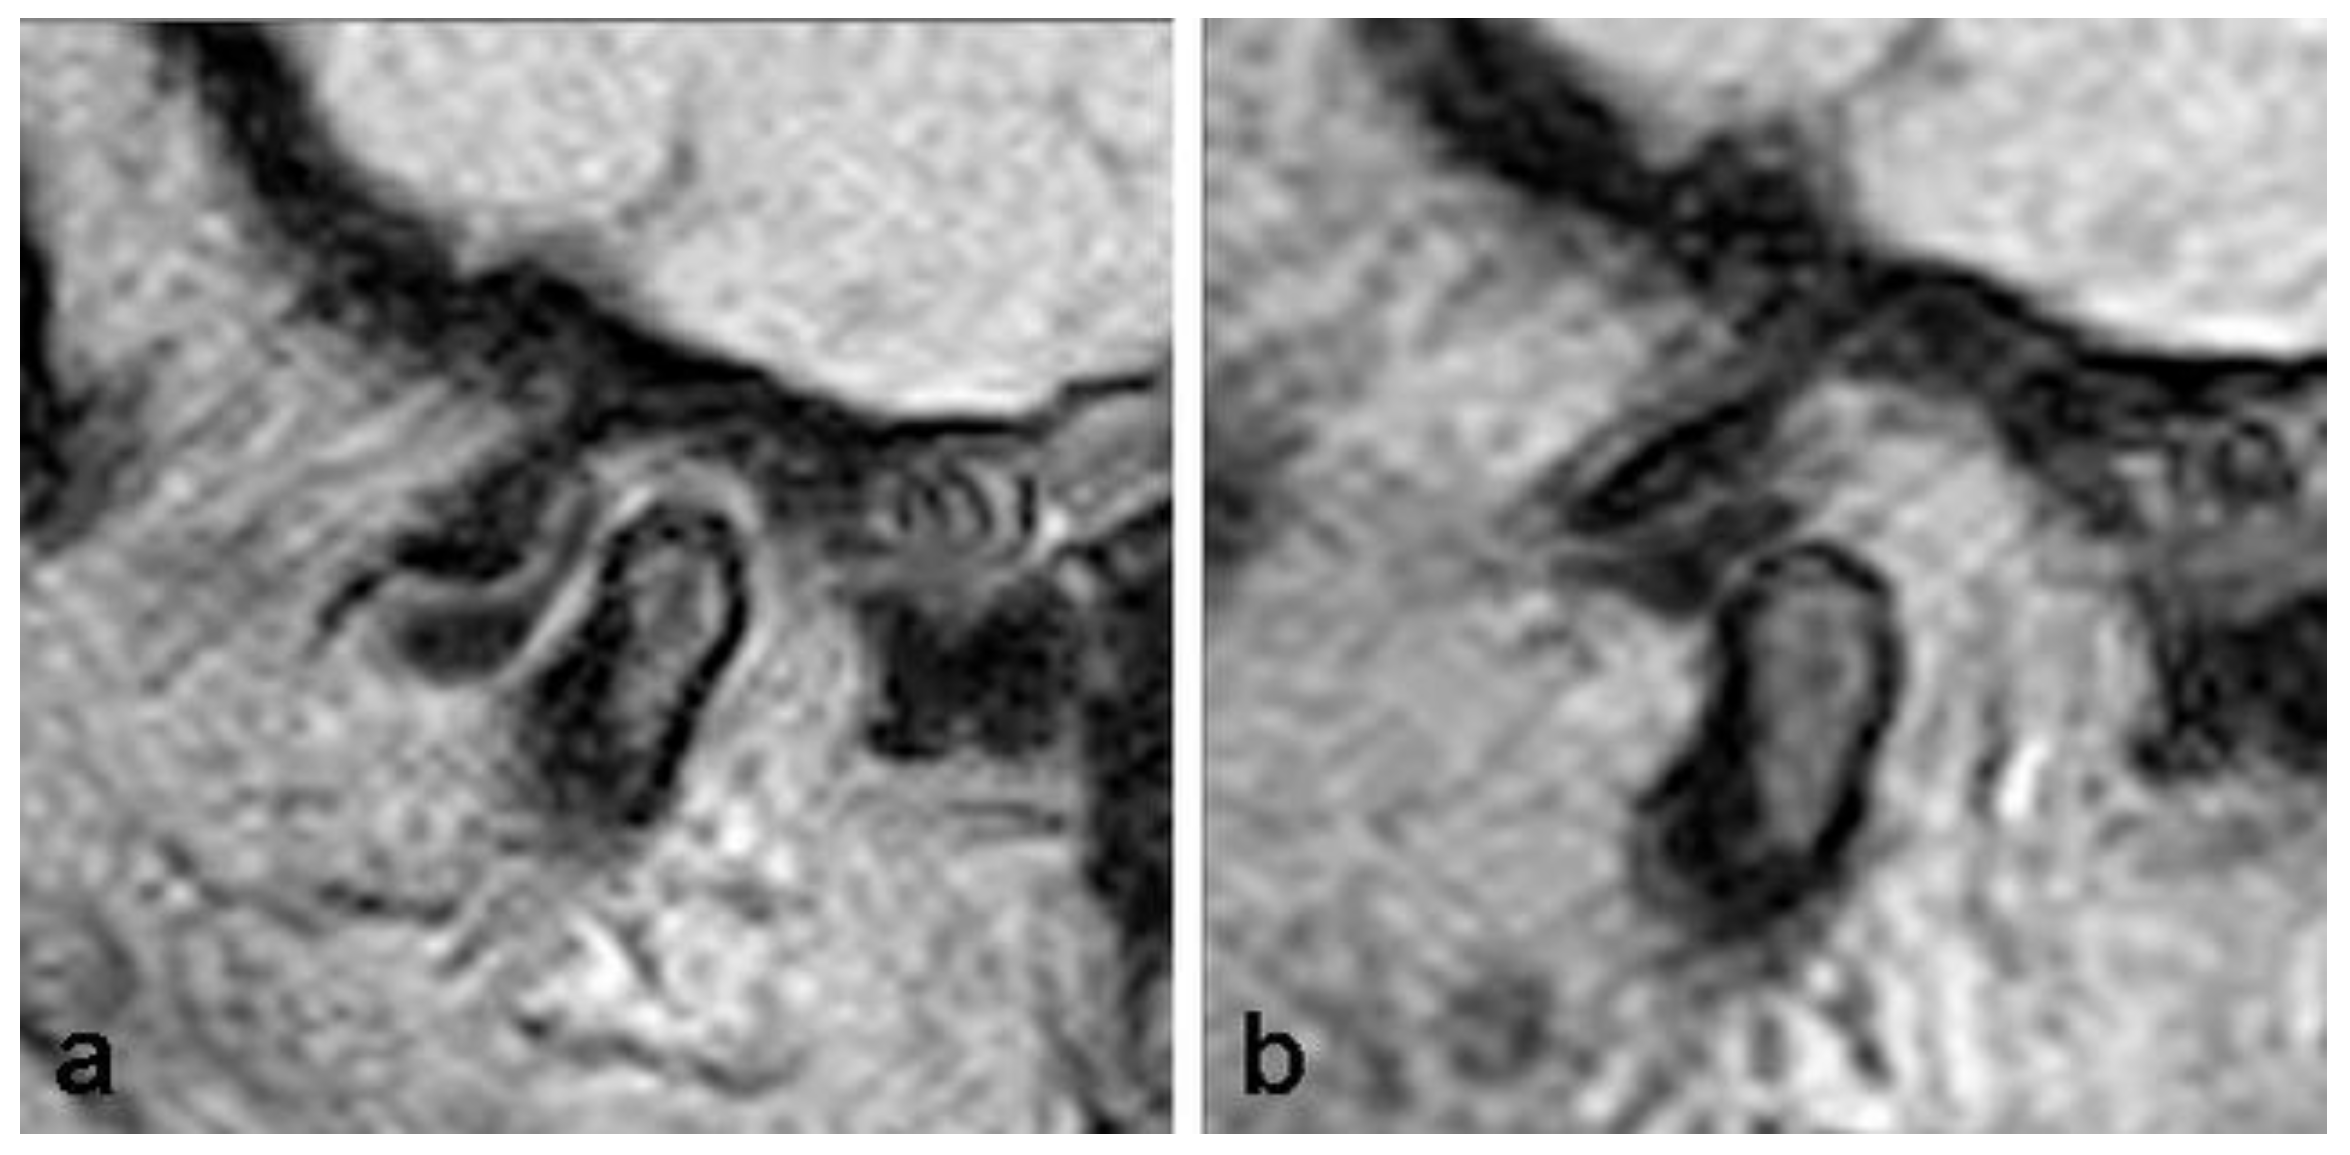

| Disc length (mm) | Normal | 145 | 9.98 | 1.73 | 6.00 | 14.00 | 1.188 | 0.307 |

| Anterior dislocation with reduction | 33 | 9.46 | 1.58 | 6.00 | 12.00 | |||

| Anterior dislocation without reduction | 12 | 10.00 | 2.76 | 4.00 | 13.00 | |||

| Total | 190 | 9.89 | 1.79 | 4.00 | 14.00 | |||